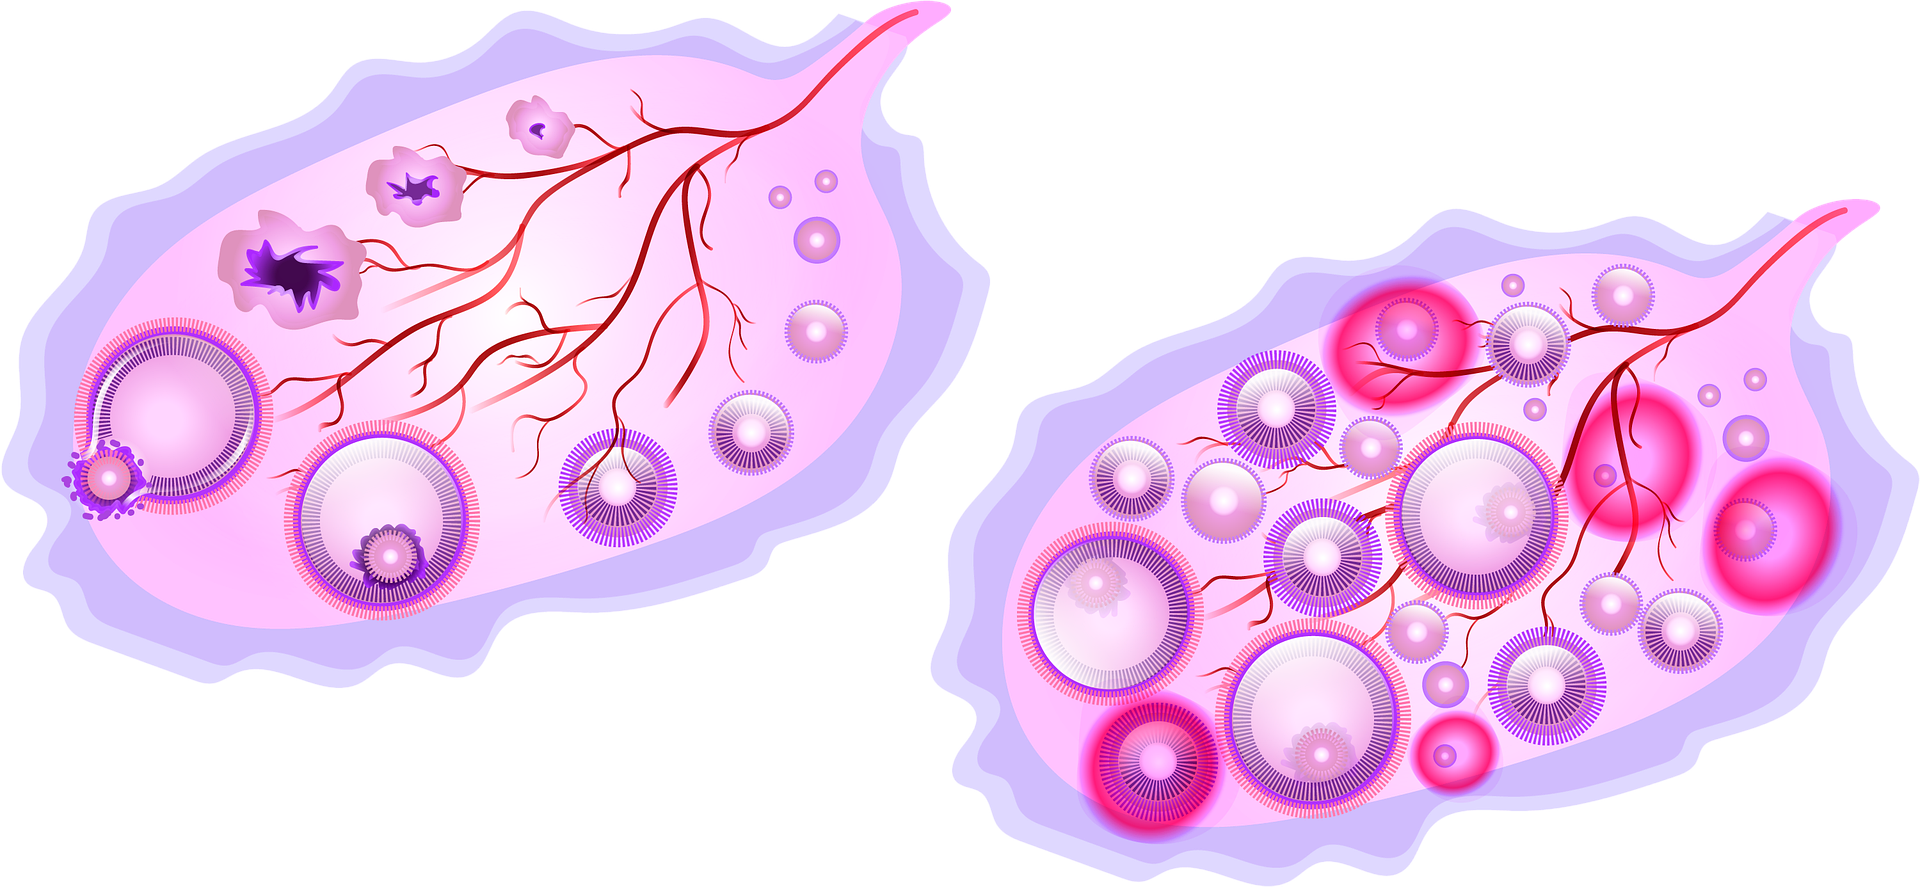

Созревание фолликула в яичнике: этапы и процессы